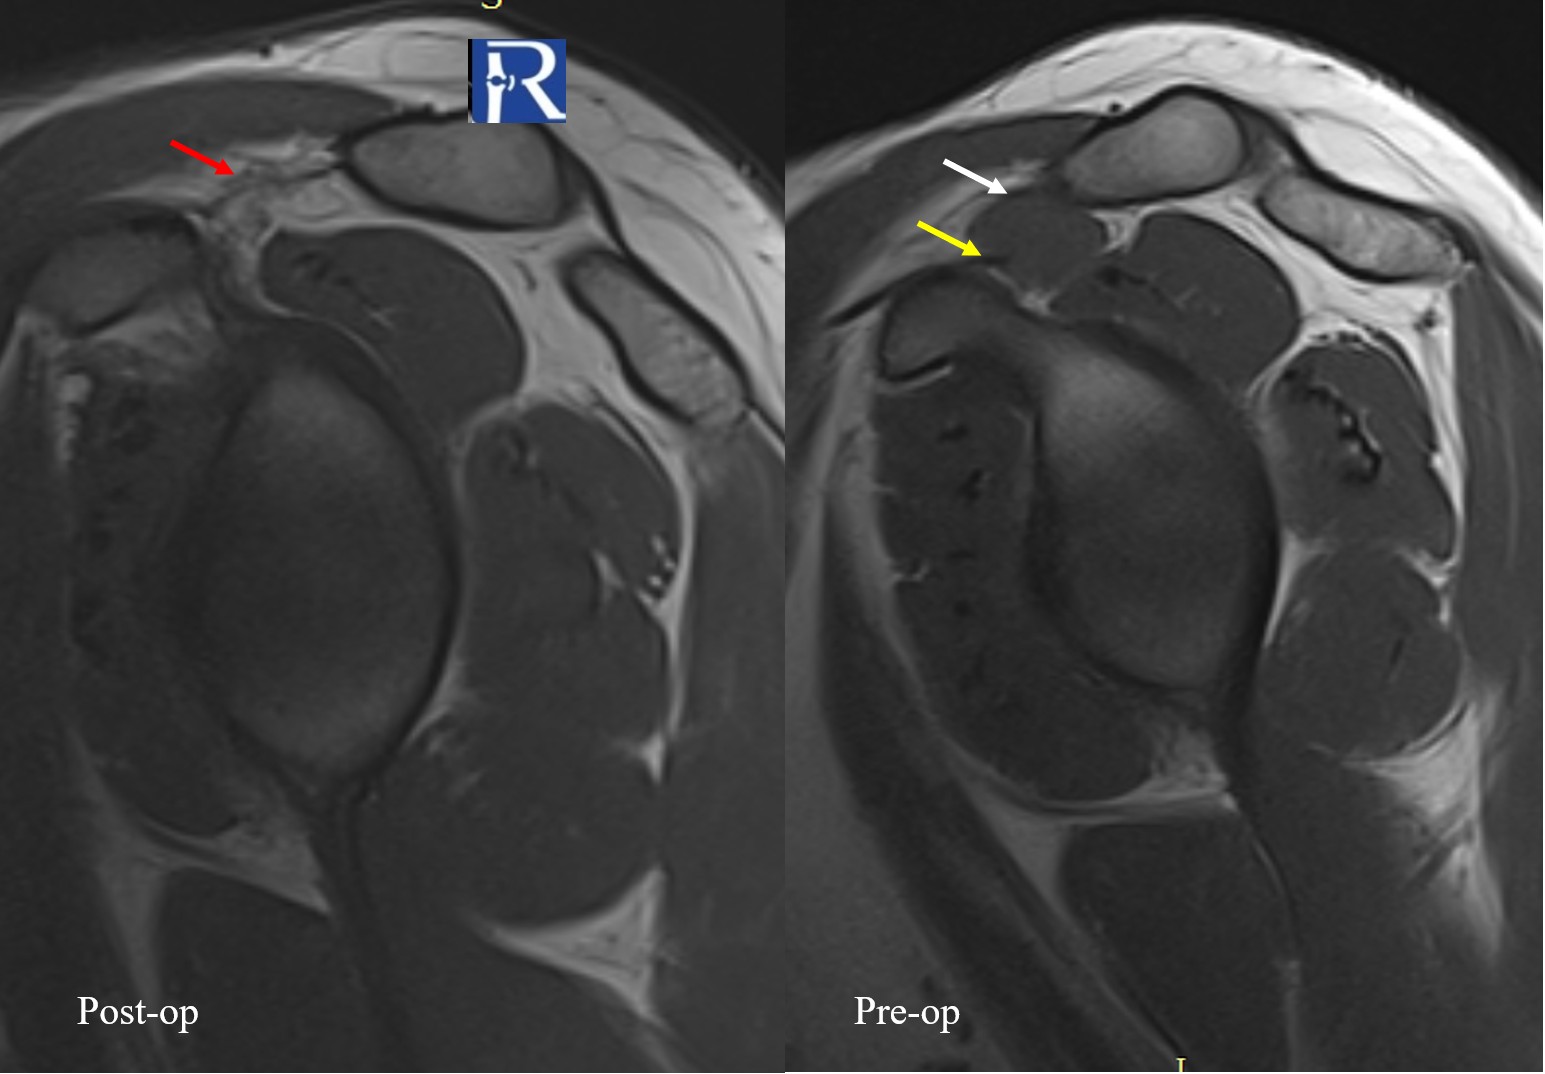

Location: Coracoclavicular space, adjacent to the supraspinatus tendon

- A well-defined solid soft-tissue mass located between the coracoclavicular and coracoacromial ligaments, immediately adjacent to the supraspinatus musculotendinous unit.

- The lesion is isointense to muscle on T1-weighted images.

- On fat-suppressed proton density sequences, the mass demonstrates intermediate to low signal intensity.

- Following contrast administration, the lesion shows marked diffuse enhancement.

- On fluid-sensitive (fat-suppressed) sequences, the lesion again exhibits intermediate-to-low signal, suggestive of hemosiderin or cellular lesion.

The combination of location adjacent to tendon/synovial structures, signal characteristics, and contrast enhancement pattern raised the suspicion for a tenosynovial giant cell tumor (TGCT).

The patient underwent surgical excision of the lesion.

Histopathological examination was consistent with a Tenosynovial Giant Cell Tumor (formerly referred to as a localized type of pigmented villonodular lesion), confirming the imaging diagnosis.